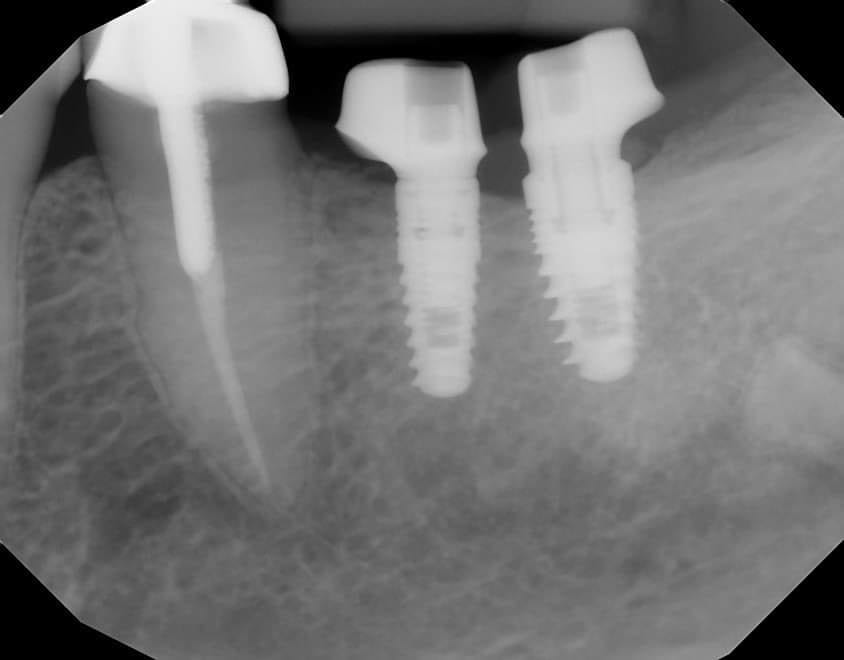

You would have struggle with analog impressions

This is THE indication for digital dentistry over analog impressions!